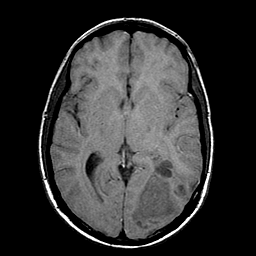

Sarcoma, MR Study #1 mr-t1 -- Slice #11

[Home][Help][Clinical] Slice 11